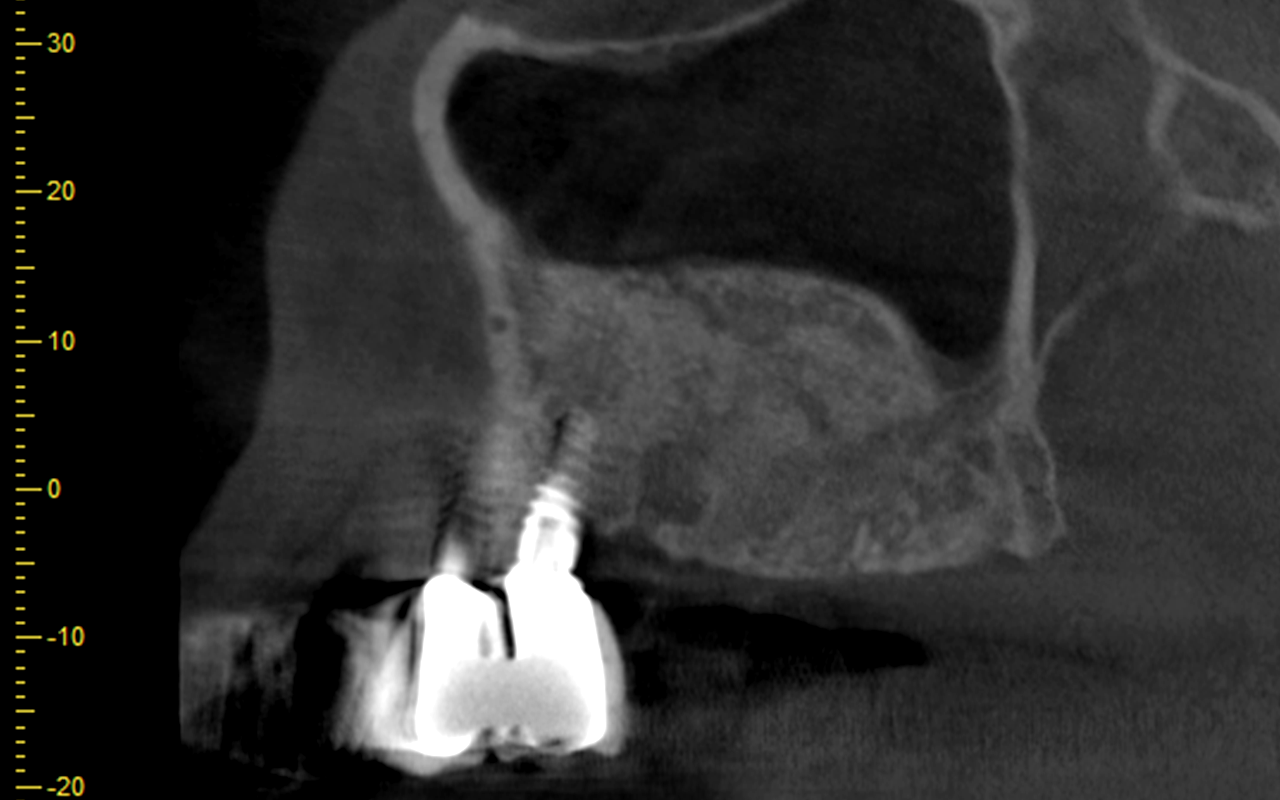

The surgical aspect will focus on advanced implant procedures, GBR vertical and horizontal grafting, Sinus augmentation, Periimplantitis and complications in implant dentistry.

1) GBR horizontal and vertical bone grafting with collagen and TR-PTFE membranes, fixations pins and screws, bone grafts, biomaterials and Growth Factors in special plastic models and fresh pig jaw models

3) Sinus bone graft procedures using the lateral and crestal lift approach